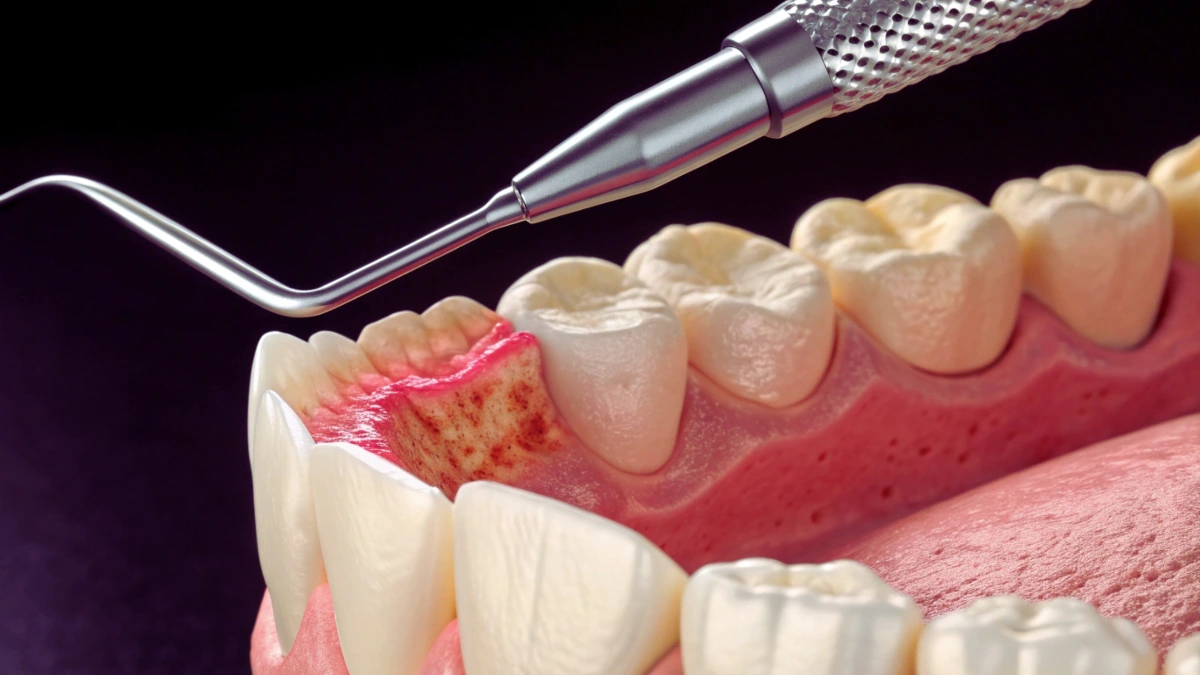

Professional cleanings remove tartar. You can’t brush this off at home. It’s a hardened plaque that harbors bacteria. Only a dentist can remove it.

Dentists catch problems early. You can’t see under your gum line. They can. Early treatment stops the disease from progressing.

Deep cleanings reverse damage. Even if you have gum disease, treatment can stop it. Intensive treatment of gum disease slows the thickening of arteries that leads to stroke.

Scaling and root planing is the gold standard. This is a deep cleaning below your gum line. The dentist removes tartar and smooths your tooth roots. This helps gums reattach to teeth.